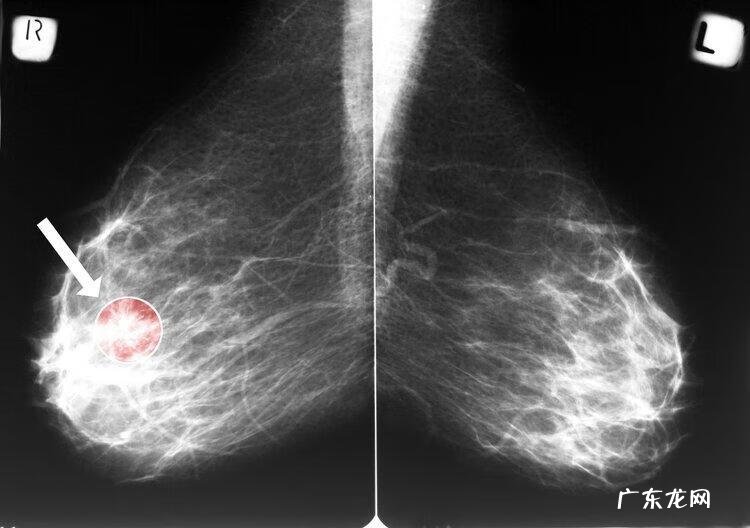

早期乳腺癌症状并不明显,也容易被大众忽视 。因此定期筛查尤为重要 。建议适龄女性,应每年进行乳腺钼靶(乳腺X线筛查)和B超检查,这也是乳腺癌常用的筛查手段 。